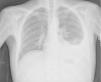

Ao exame objetivo (Maio de 2009) apresentava mau estado geral, peso de 45 kg, febre (temperatura auricular de 39,5°C) e taquicardia. Estava normotenso, com saturações de 99% (FiO2-21%) em oximetria de pulso. À auscultação pulmonar de salientar a diminuição dos sons respiratórios na base do campo pulmonar esquerdo. A avaliação analítica efetuada mostrava forma leucocitária normal (CD4+ - 269mm3), anemia (11,9g/dL) e aumento da proteína C-reactiva (24mg/dL). A radiografia de tórax mostrava opacidade na base esquerda sugestiva de derrame pleural (fig. 1) e efectuou Tomografia Computorizada toraco-abdominal que confirmou a presença de derrame pleural, não mostrou alterações pleuroparenquimatosas e detetou massa mesentérica com 5,5cm de diâmetro.